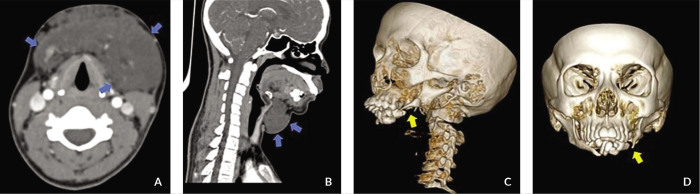

Gorham-Stout病是一种罕见的溶骨性疾病,其病理生理机制尚不清楚。它表现为以骨基质丧失和畸形血管增生为特征的病变。目前,没有金标准的诊断评估方案,它是通过临床、组织病理学和放射学结果的混合诊断的。我们报告一个19岁的女性与Gorham-Stout病表现为8年进行性软组织肿块在下颌骨。广泛的骨溶解下颌骨与集群的下颌牙列是注意到在计算机断层扫描(CT)成像。她的病例在一个多学科会议上讨论,她的治疗是放疗后手术±重建。我们使用基于ct的三维规划技术,在20个疗程中对相关区域给予40 Gy的治疗。治疗后,6周复查CT以重新评估疾病进展或稳定,然后进行手术切除。截至2021年10月31日,治疗后48个月无复发迹象。对Gorham-Stout病的明确诊断具有挑战性,多学科团队方法可以帮助确定具有最佳结果的治疗选择。

Gorham-Stout disease is a rare osteolytic disorder with an unclear pathophysiology. It presents as lesions characterized by the loss of the bony matrix and the proliferation of malformed vasculature. At present, there are no gold-standard diagnostic evaluation protocols and it is diagnosed through a mixture of clinical, histopathologic, and radiographic findings. We report a case of a 19-year-old female with Gorham-Stout disease presenting with an 8-year progressive soft tissue mass in the mandible. Extensive osteolysis of the mandible with clustering of the mandibular dentition is noted on computed tomography (CT) imaging. Her case was discussed in a multidisciplinary conference and her treatment was radiotherapy followed by surgery ± reconstruction. We used a CT-based three-dimensional planning technique to give 40 Gy over 20 treatment sessions to the involved areas. Post treatment, a repeat CT was done at six weeks to reassess for disease progression or stabilization, followed by surgical excision. As of 31 October 2021, no evidence of recurrence is noted 48 months after treatment. Arriving at a definitive diagnosis with Gorham-Stout disease is challenging and a multidisciplinary team approach can help determine the treatment choice with best outcomes.